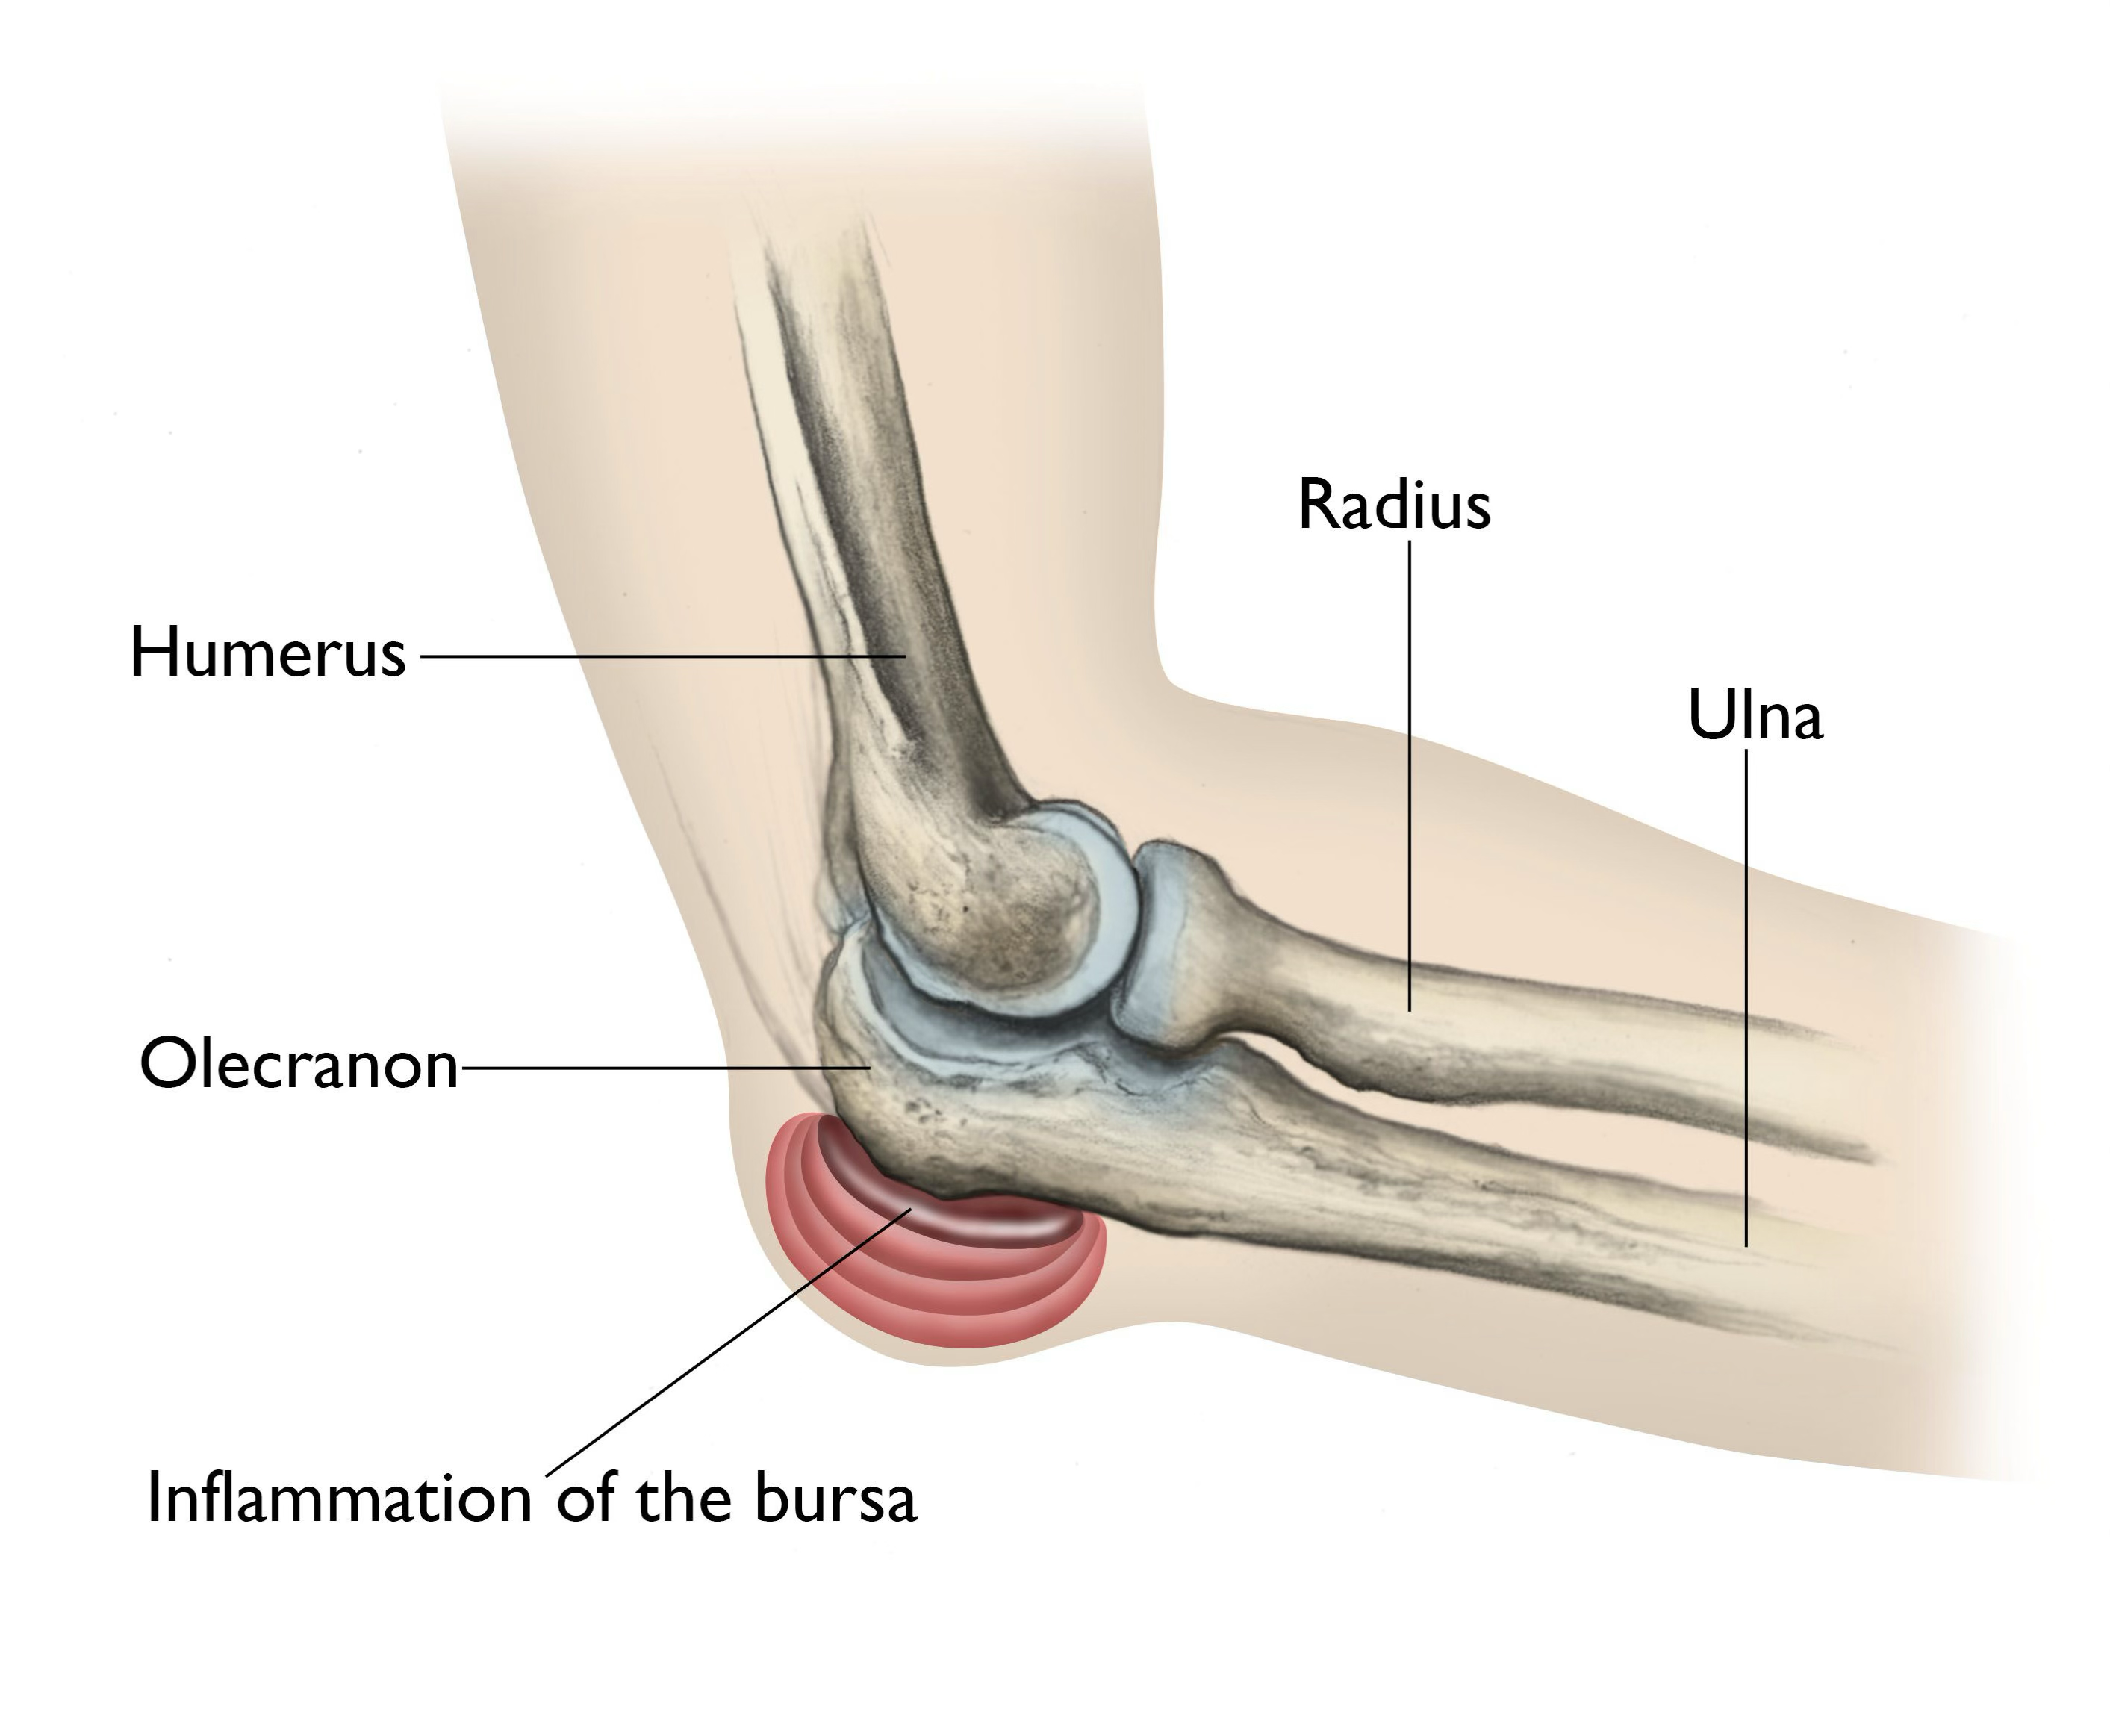

olecranon bursitis

as the bursae is superficial, we tend to injure it a lot with direct blows

symptoms of olecranon bursitis

mild pain, pressure, swelling, tenderness

treatment of olecranon bursitis

compress and ice it

if swelling doesn’t resolve, we can drain it

if athlete, we tend to pad the area so it doesn’t keep happening